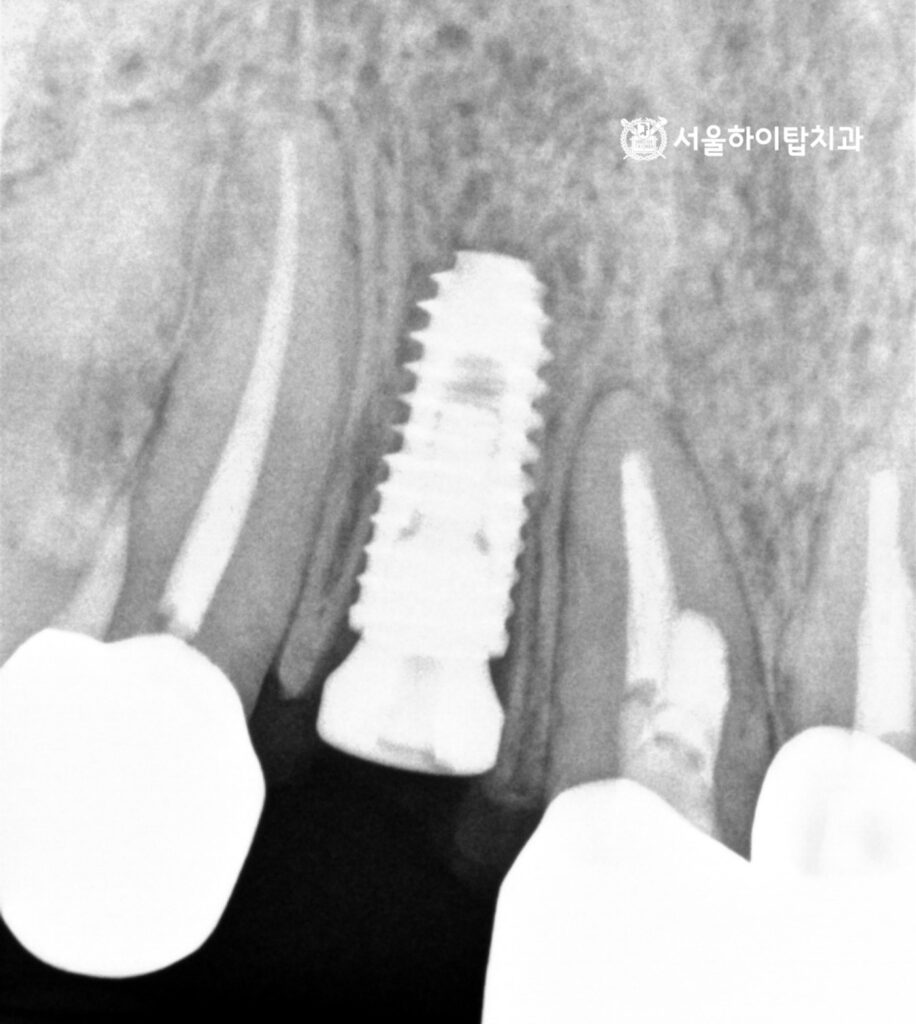

위 엑스레이 사진을 살펴보면,

전치부 치아 특성상 치조골 폭이 다소 좁음에도 불구하고,

앞서 진행한 가상 시뮬레이션을 기반으로 안전하고 정확한 위치에

임플란트가 식립된 모습을 확인할 수 있습니다.

백운역 치과 에서 PA 사진으로 확인해도,

주변 인접 치아나 치주 조직에 손상 없이 정확하게 식립된 모습을 확인할 수 있습니다.